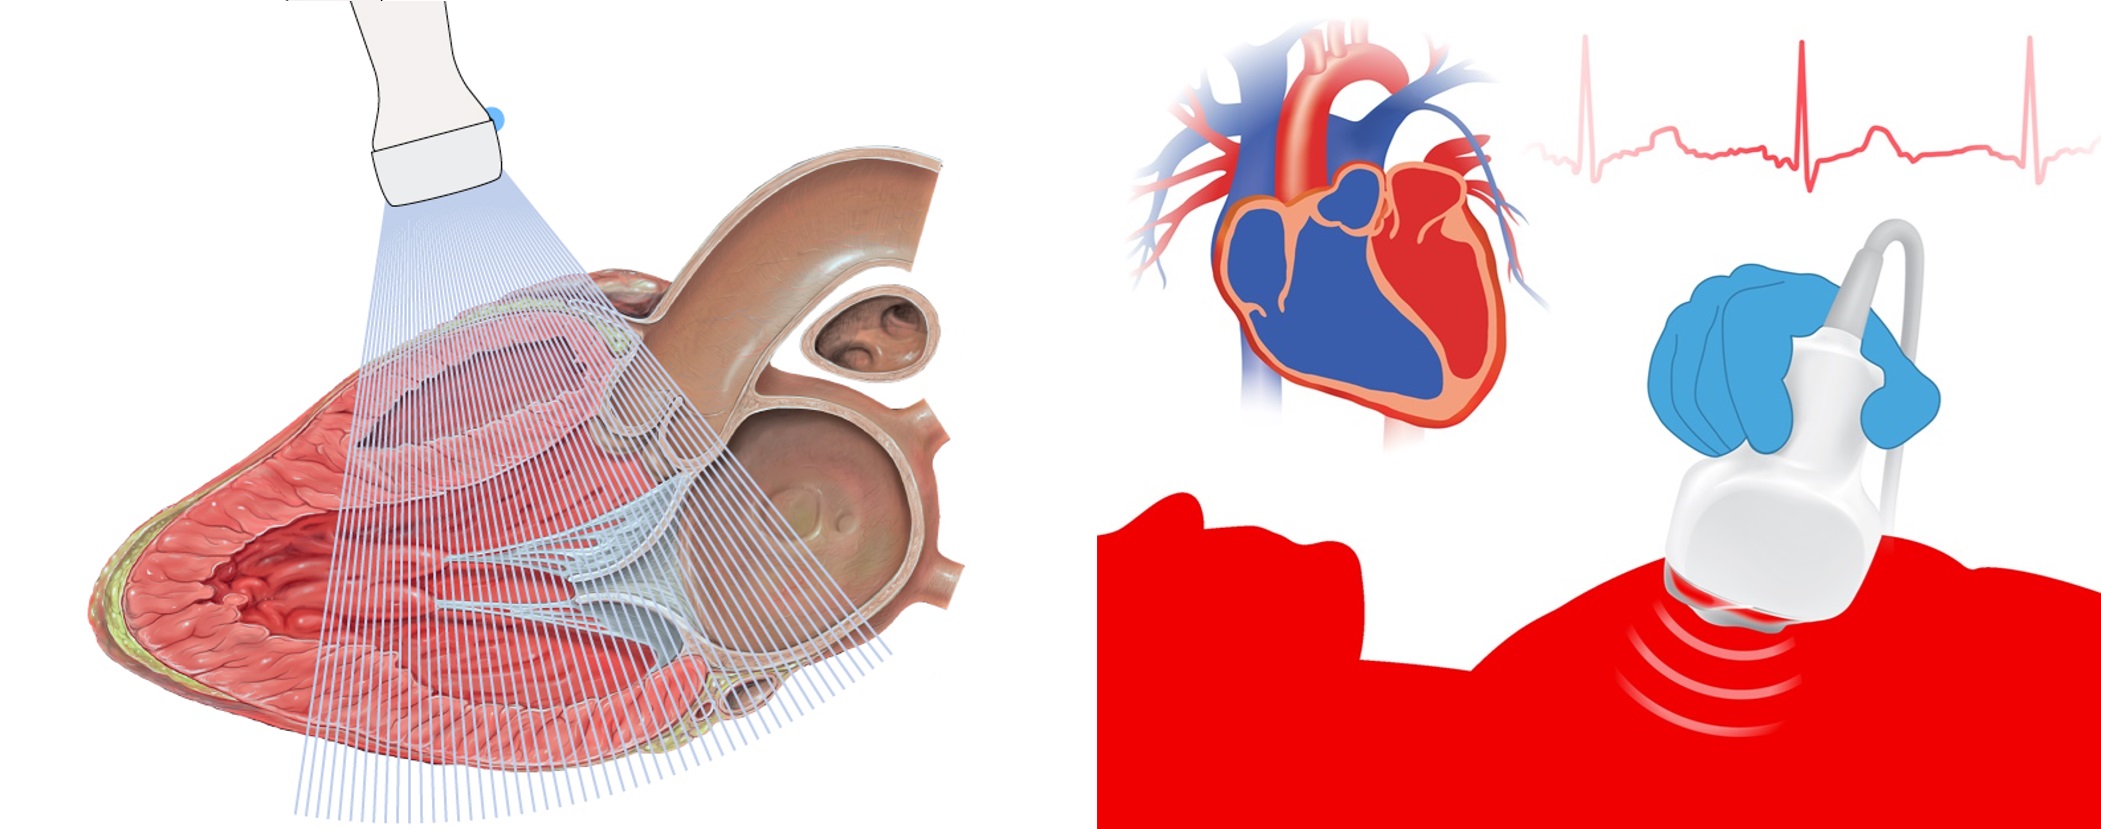

Phòng khám đang thực hiện kỹ thuật Siêu âm tim qua thành ngực để kiểm tra sức khỏe và phát hiện các bất thường tại tim.

Hãy cùng chúng tôi tìm hiểu sơ lược về kỹ thuật này.

Minh họa kỹ thuật siêu âm tim

Siêu âm tim là một phương pháp thăm dò không xâm lấn, không gây đau hay gây hại cho sức khỏe. Bác sĩ sử dụng kỹ thuật này để theo dõi nhịp tim,

cấu trúc, kích thước và chức năng tim thông qua hình ảnh được ghi lại.

Các phương pháp kiểm tra, chẩn đoán bệnh lý tim cũng không ngừng phát triển. Trong đó, siêu âm tim không phải là kỹ thuật

mới song vẫn giữ vai trò quan trọng trong thăm khám, chẩn đoán bệnh lý tim mạch.

Vì thế siêu âm tim vẫn thường được chỉ định đầu tiên khi bác sĩ nghi ngờ có vấn đề sức khỏe tim mạch bất thường,

nếu cần thêm thông tin sẽ yêu cầu xét nghiệm bổ sung.

Trong quá trình làm siêu âm tim, bác sỹ sẽ dùng một hoặc một số đầu dò thích hợp để soi vào tim qua thành ngực hoặc từ vị trí khác để

lấy hình ảnh của tim thông qua sóng siêu âm.